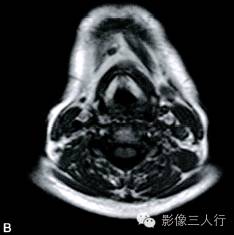

A~B. T1WI横断位;C~D. T2WI压脂横断位; E~F. T1WI压脂增强横断位;G. HE×100

卵圆形结节影位于舌骨中线,T1WI呈低信号,T2WI压脂序列呈稍高信号,信号均匀。增强后明显均匀强化,约1.3cm×0.8cm×1.6cm,其右前方下颌间隙内亦见一小结节,约0.7cm×0.4cm×0.5cm,信号特点与舌骨中线结节大致相同。颈部软组织结构清楚,未见异常信号影,气管居中,无受压或移位。颈部MRI平扫两侧见正常甲状腺组织,信号欠均匀(图A~F)。